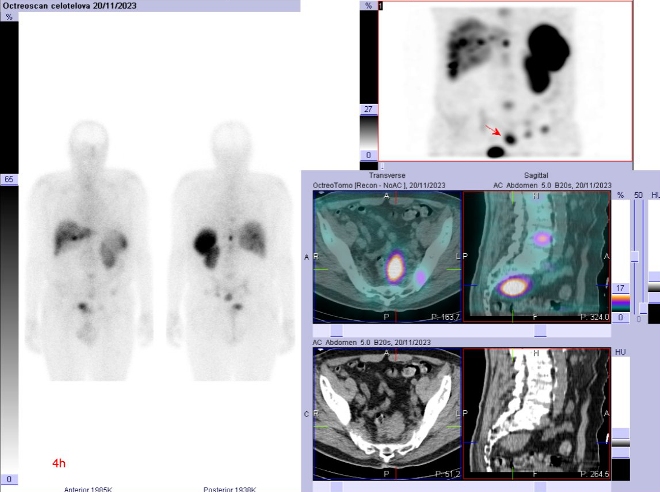

Scintigrafie Octreoscanem:

I. v. jsme aplikovali 190 MBq analogu somatostatinu značeného 111In

(přípravek OctreoScan firmy Curium Netherlands B. V.) a provedli pomocí hybridní tomografické scintilační kamery Symbia T2 firmy Siemens opatřené kolimátory pro střední energie planární celotělovou scintigrafii a cílenou tomografickou scintigrafii (SPECT) břicha a pánve kombinovanou s CT za 4 a 24 hod.

(obr. 1-5).

/ Obr. č. 1: Celotělová scintigrafie a SPECT/CT za 4 hod. po aplikaci OctreoScanu.

Popis: pozorujeme patologicky zvýšenou depozici radiofarmaka:

- v několika fokusech skeletu (nejkontrastněji v proc. spinosus Th10, dále v hrotu pyramidy os temporale vlevo, tělech Th3, Th6, Th8, Th12, L4, kosti kyčelní vlevo), vícečetně v žebrech oboustranně, v ldCT obraze mnohočetná smíšená převážně sklerotická ložiska

- nehomogenní kumulace v játrech, místy až s fokusy, nejnápadnější je v levém laloku ventromediálně

- v ložisku v malé pánvi pararektálně vlevo vel. cca 48x38mm

Akumulace v žlučníku, slezině, levé ledvině, močovém měchýři a střevních kličkách představuje fyziologickou distribuci.

Závěr: Mnohočetná ložiska patologicky zvýšené denzity somatostatinových receptorů, které odpovídají neuroendokrinní nádorové tkáni a generalizaci onemocnění (výrazně skelet, v ložisku v pánvi pararektálně a velmi suspektně v játrech).